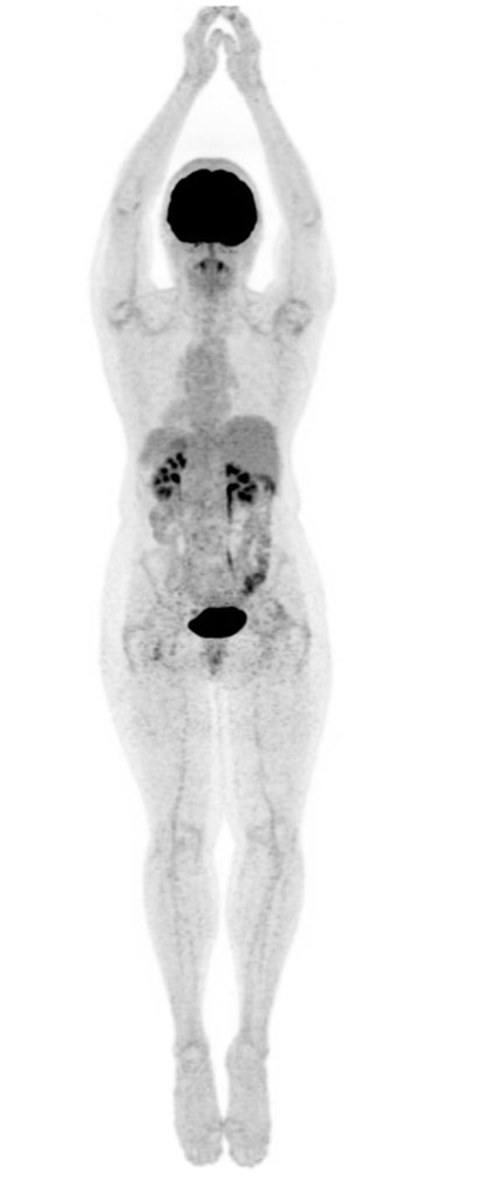

While FDG is an analog of glucose, the fluoride in NaF incorporates into the hydroxyapatite (mineral component) of bone by replacing a hydroxyl group to form fluoroapatite. F18-NaF PET bone scan commonly demonstrate non-malignant, scattered focal uptake within the spine, bilateral knees, feet and shoulder joints, consistent with degenerative bone remodeling. Normally, there is no brain uptake on NaF PET scanning.

A) Whole-body F18-FDG PET scan maximum intensity projection (MIP) bone demonstrates intense uptake in the brain and renal excretion. Mild activity is seen within the bone marrow. B) Whole-body F18-NaF PET bone scan maximum intensity projection (MIP) demonstrates scattered focal uptake within the spine, bilateral knees, feet and shoulder joints consistent with degenerative bone remodeling. Note: Intense uptake is seen within the brain on FDG PET and no uptake is seen on NaF PET. |